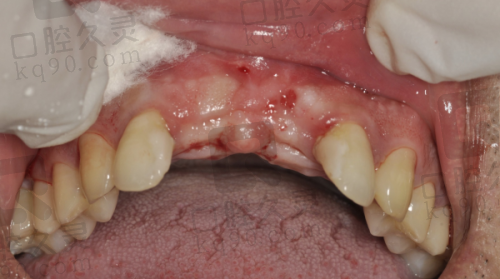

据统计,鼎植口腔的医生平均从业经验超过8年,种植牙团队尤其硬核。例如在上海鼎植,有位高振华院长,别名“穿颧穿翼种植技术”的发明人之一,干过的优质病例包括——全口缺牙、高龄老人(80+)、骨量重度不足的极限挑战对象,你以为这是《牙医生存大挑战》拍剧组的么?不,这是他们日常操作。